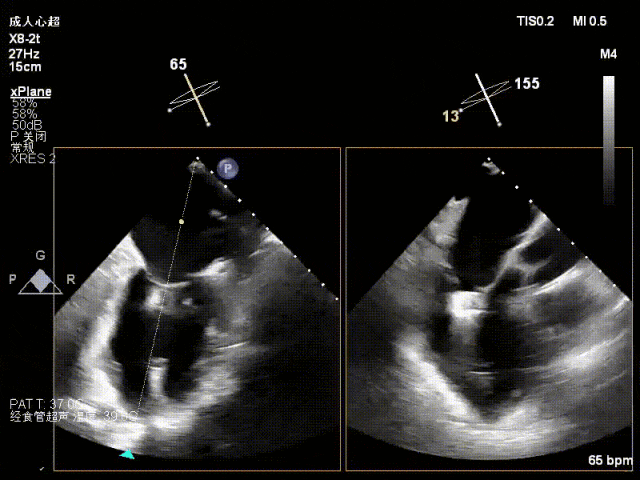

术前心超

二尖瓣前叶脱垂,功能性二尖瓣反流(FMR),新分型:DAA型

A2瓣叶脱垂、瓣尖对合错位,反流2区,MR 4+,VC:5×12mm

术中超声(关键步骤)